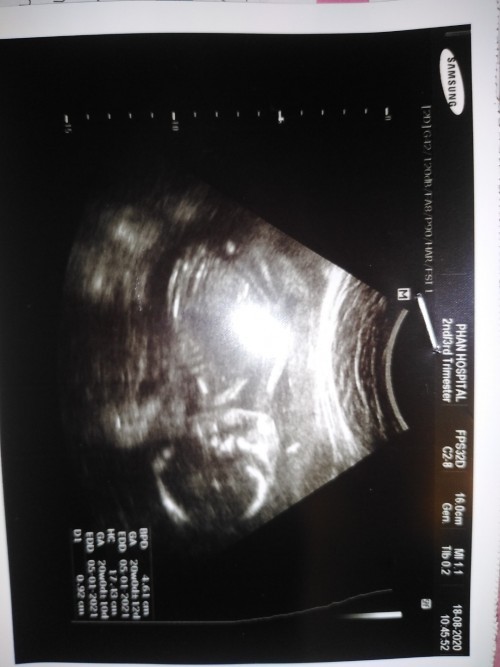

แม่ๆคลอดปี64 ลูกกี่วีคกันแล้วคะ บ้านนี้กำหนดผ่าคลอด 22 กุมภาพันธ์ 64 อาการแพ้ท้องเริ่มดีขึ้นแล้ว สู้ๆไปด้วยกันนะคะ✌🏻✌🏻✌🏻🥰🥰